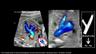

Three and Four Dimensional Ultrasound in Fetal Echocardiography

Elena Sinkovskaya, M.D., Ph.D., RDMS, RDCS